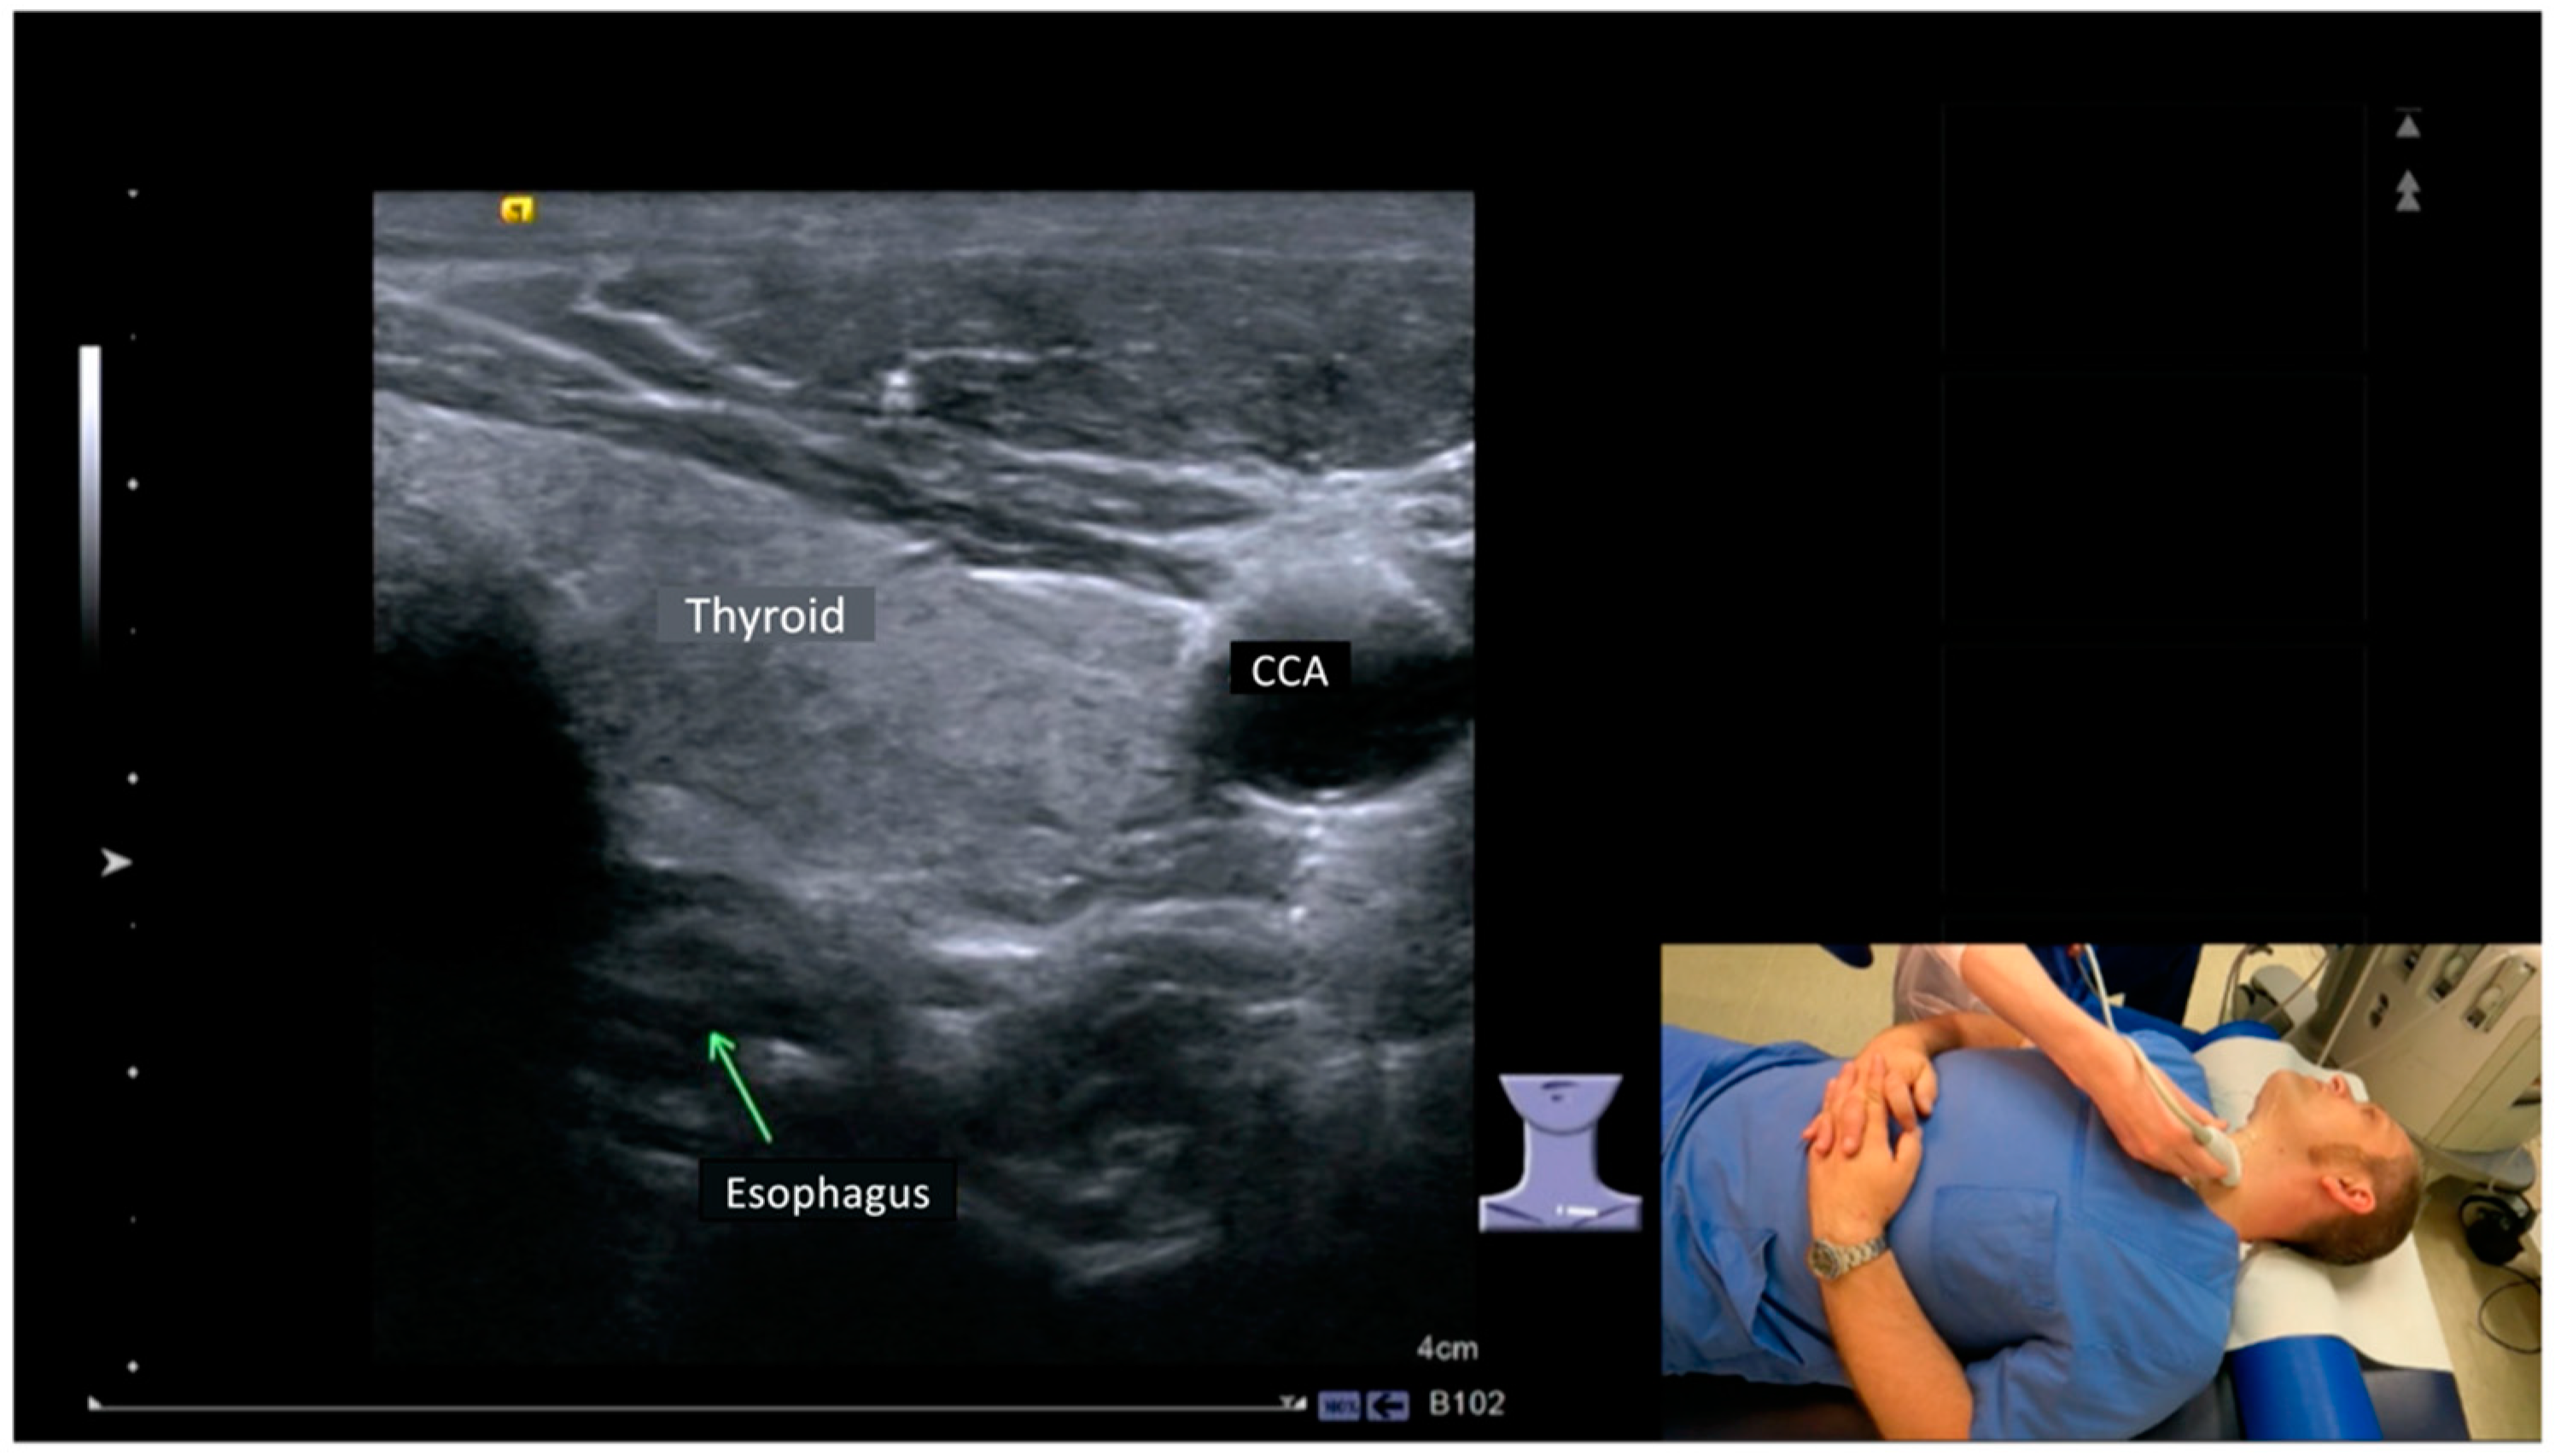

All students gave informed consent to participate in the study. Twenty-two students were randomly assigned to two groups, one group being taught in person and the other group in a video-based course. As part of our university college curriculum, the ultrasound course is designed for students within 45-min sessions. Therefore, each group was trained in pairs for 90 min. The students performed the HANUS examination on each other. A manual with a step-by-step guide on how to perform a detailed HANUS examination had been given to each student 48 h prior to the course start. This guide included the most important anatomical landmarks in HANUS, displaying the structure in the ultrasound image and the corresponding position of the patient and the transducer (Figure 1).

Figure 1. Excerpt from the step-by-step guide on how to perform a detailed HANUS examination. Ultrasound transducer and patient position were displayed in the lower right part of the screen, the standard planes were shown in the center of the screen, and the most important anatomical landmarks were labeled (ultrasound image showing the left lobe of the thyroid gland (thyroid), the esophagus, and common carotid artery (CCA)).